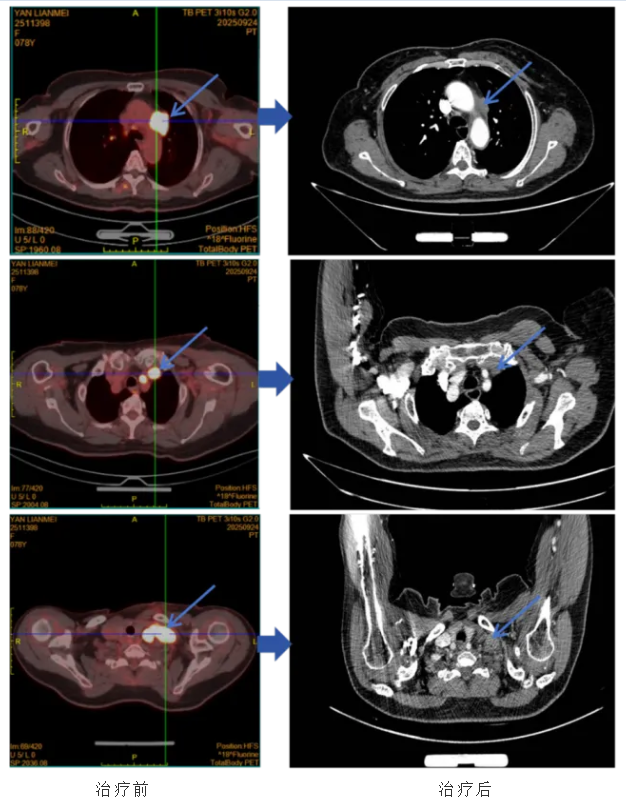

2025年9月,闫女士因“左手肿胀麻木2天”在当地医院就诊,胸部CT检查发现左侧中上纵隔占位性病变,伴左侧腋窝、锁骨上及纵隔内多发肿大淋巴结。随即行超声引导下左锁骨上淋巴结穿刺,查见恶性肿瘤。为寻求精准救治,闫女士来到山东第一医科大学附属肿瘤医院,求助于王海永教授团队。PET/CT检查结果显示:左前纵隔、左侧锁骨区、左侧颈根部多发肿块及结节,均考虑为相同性质恶性肿瘤。病理会诊结果明确诊断为转移性分化差的癌,倾向SMARCA4缺失的低分化腺癌。由于基因检测未发现突变,患者并无靶向治疗机会。病情已发展至晚期,高龄加上晚期病情,让患者的诊疗之路充满考验。我院第一时间为闫女士组织多学科会诊(MDT),综合评估患者的年龄、身体状况、病情分期等关键信息后,给出专业诊疗意见:建议患者优先入组针对SMARCA4缺失型肺癌的临床试验。随后,闫女士顺利入组王海永主任发起的“艾帕洛利托沃瑞利单抗联合含铂化疗和盐酸安罗替尼治疗SMARCA4缺失的晚期或转移性非小细胞肺癌的单臂、II期探索性研究”。完成2周期治疗后,患者于2025年12月24日行胸部CT复查,结果显示左前纵隔肿瘤及左侧锁骨区、左侧颈根部转移淋巴结较前明显缩小,治疗效果显著。王海永主任及其团队考虑患者高龄,为避免严重不良反应的发生,予以积极对症处理,延长住院时间,患者耐受性良好。截至目前,闫女士已完成8个周期的规范治疗,顺利进入维持治疗阶段,病情持续稳定,且在整个治疗过程中患者耐受性良好,未出现明显不良反应,生活质量得到有效保障。